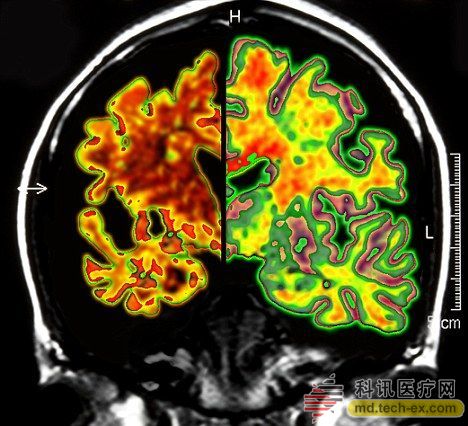

在手術(shù)中,所有病患的腦部將被植入電極,這些電極與一個(gè)類似起搏器的裝置相連接,能夠每秒鐘發(fā)出130次電脈沖。羅森博格表示,病人并不會(huì)感受到電脈沖的存在。 研究人員表示,所有接受臨床試驗(yàn)的病人同時(shí)都會(huì)被植入這個(gè)“起搏器”裝置。其中,一半病人的“起搏器”將于手術(shù)后兩周開啟,而另一半病人的要在手術(shù)后一年才會(huì)開啟。目前,參加臨床試驗(yàn)的病人和醫(yī)生并不知道分組情況。 其實(shí)早在2010年,加拿大就已經(jīng)對這種大腦“起搏器”展開臨床試驗(yàn)。當(dāng)時(shí),有6名輕微老年癡呆癥患者參加。當(dāng)時(shí)的試驗(yàn)結(jié)果顯示,在13個(gè)月的觀察期中,這些病患的葡糖糖代謝速度持續(xù)上升,這也就說明他們的大腦神經(jīng)元正在工作。而在同時(shí)期內(nèi),大部分老年癡呆癥患者的葡萄糖代謝水平則是在不斷下降。